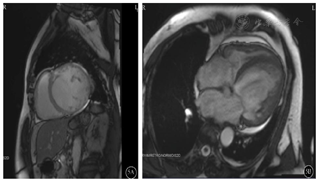

在考虑使用靶向生物制剂之前,我们决定再次对该患者进行多维评估,特别是共病的筛查。完善心肌标志物、心脏彩超、MRI心脏功能(图4,图5)增强扫描并请心内科专家阅片及评估后考虑诊断"扩张型心肌病、心功能Ⅲ级",予以双腔ICD置入术,同时行强心、利尿、抑制心室重构等对症治疗,哮喘方面我们也成功将激素减量至信必可80 µg/4.5 µg 1揿,2次/ d单药吸入治疗。